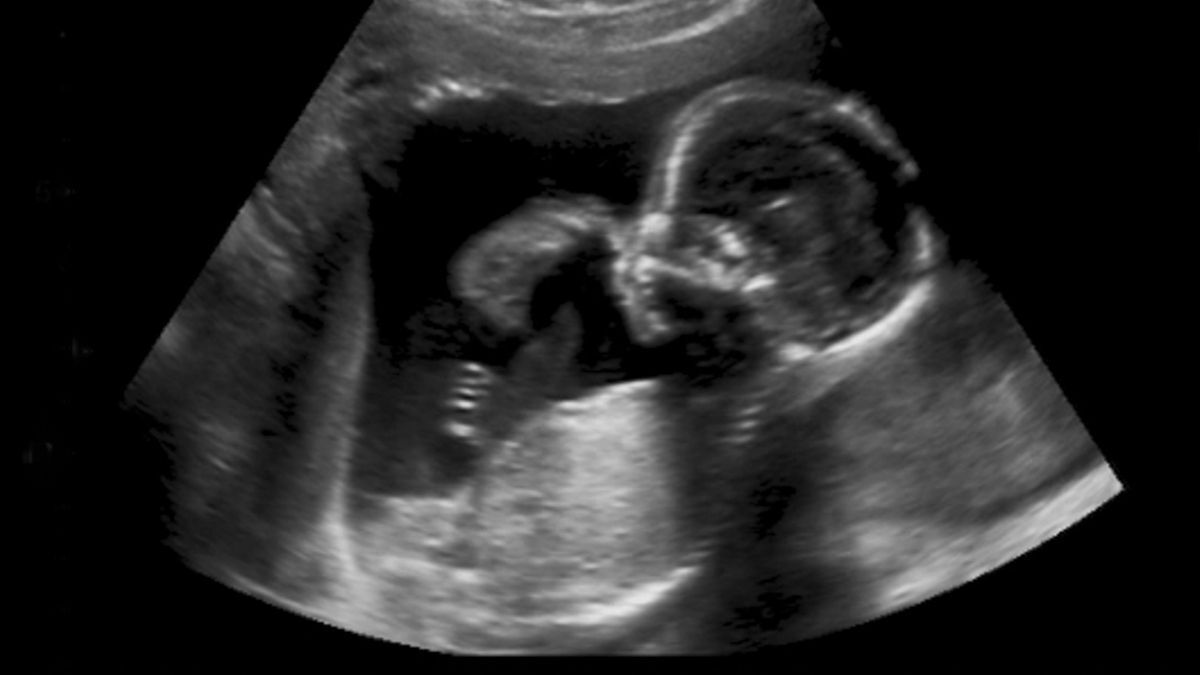

La Ecografía y examen de sangre

Se trata de las formas más certeras y menos invasivas para determinar el sexo de tu bebé.

La primera de ellas, la ecografía, consiste en verificar a través de un ultrasonido la morfología o el cuerpo ya formado del bebé. Para la misma se recomienda esperar a las 20 semanas de gestación y así obtener una imagen más precisa.

En la segunda forma, basta con recoger una muestra de sangre de la mujer embarazada y a partir de su análisis genético determinar la presencia del gen masculino o del gen femenino. Puede realizarse de manera efectiva a partir de la octava semana de embarazo.